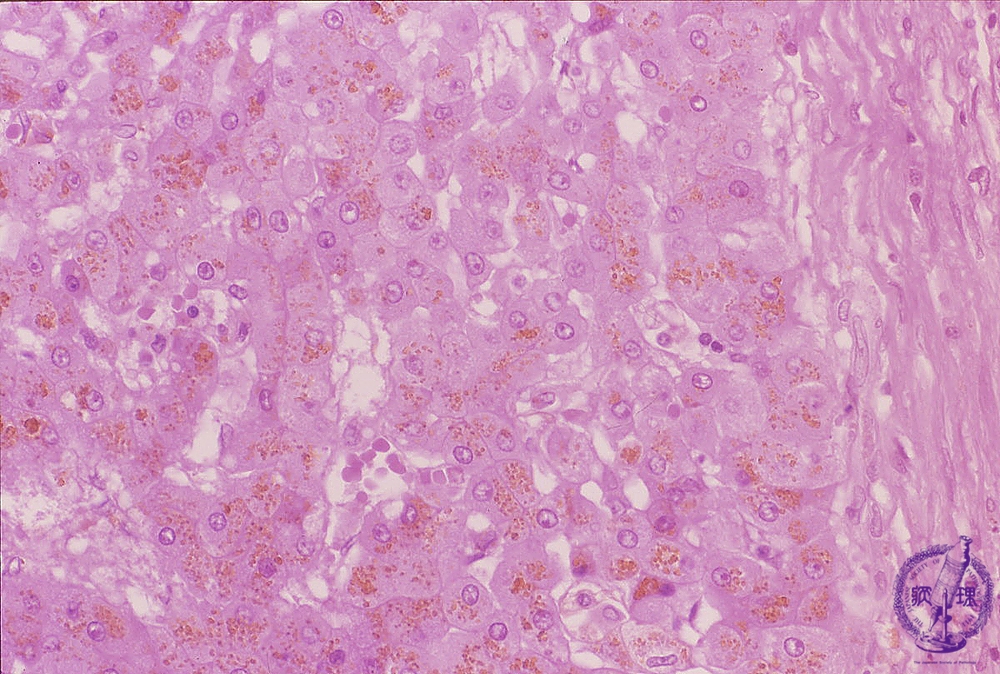

ヘモクロマトーシスの診断を確定するために肝生検が必要になる場合があります。

生検では、肝臓の小片を採取して顕微鏡で検査します。病理学者は、肝臓内の鉄の沈着や瘢痕組織の範囲を検査できます。